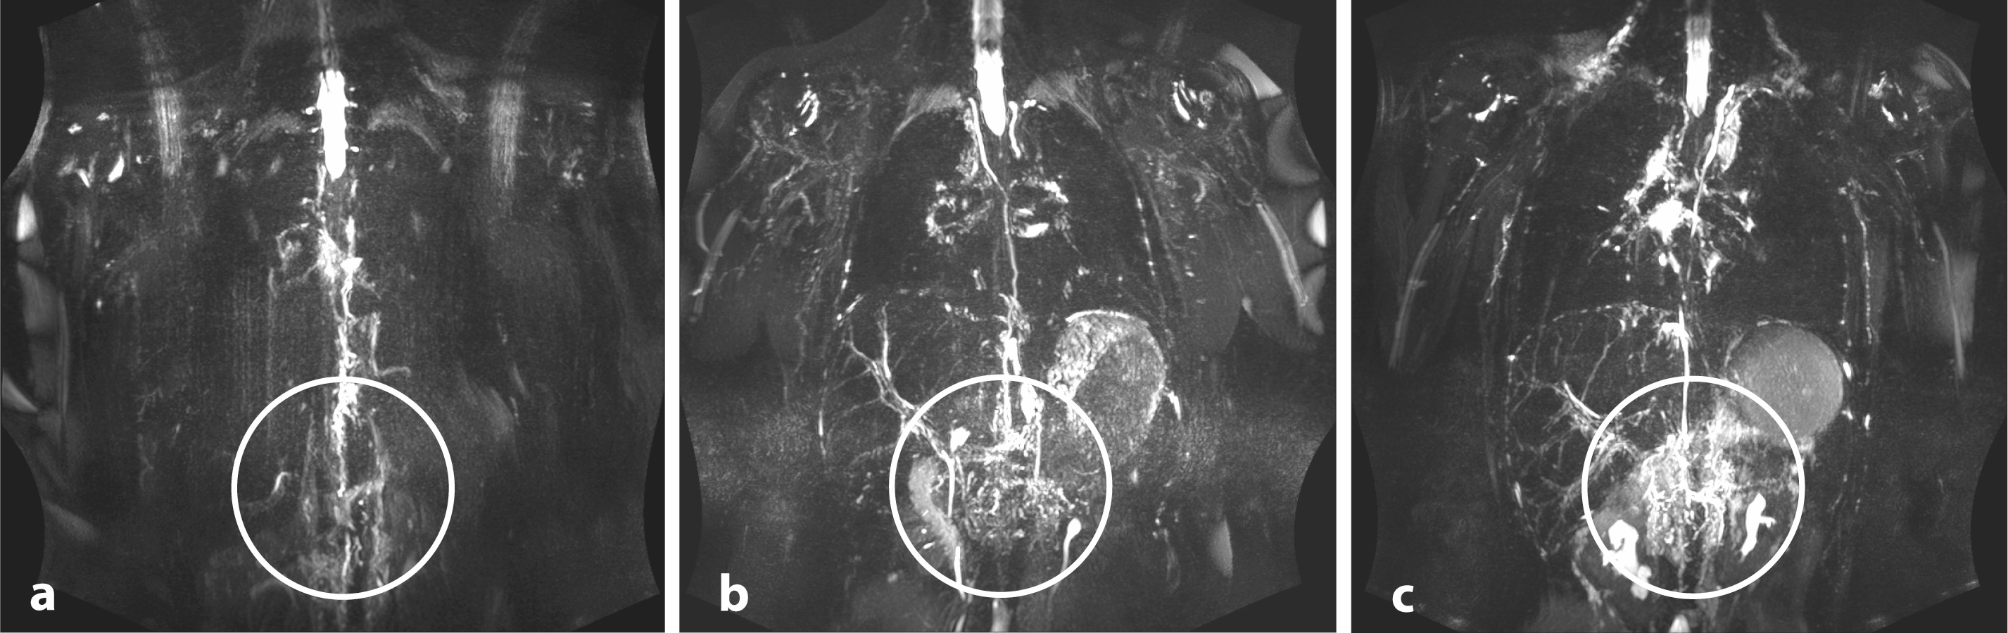

Fig. 2

Classification according to the number of delineated abdominal lymphatic vessels (nav). (a) Type 1: nav < 3 abdominal vessels defineable; (b) type 2: nav = 4–6 abdominal vessels defineable; (c) type 3 nav > 6 abdominal vessels or oedematous change/ pronounced ascites obscuring the lymphatic vessels.